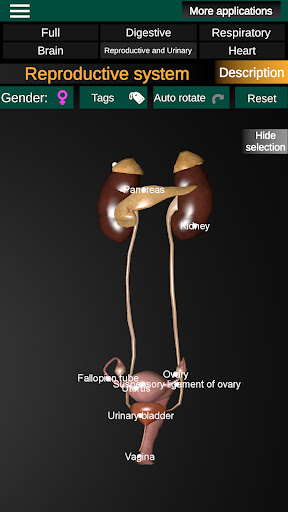

* Репродуктивна система, яка включає чоловічі та жіночі репродуктивні органи.

* Порівняйте чоловічі та жіночі органи.